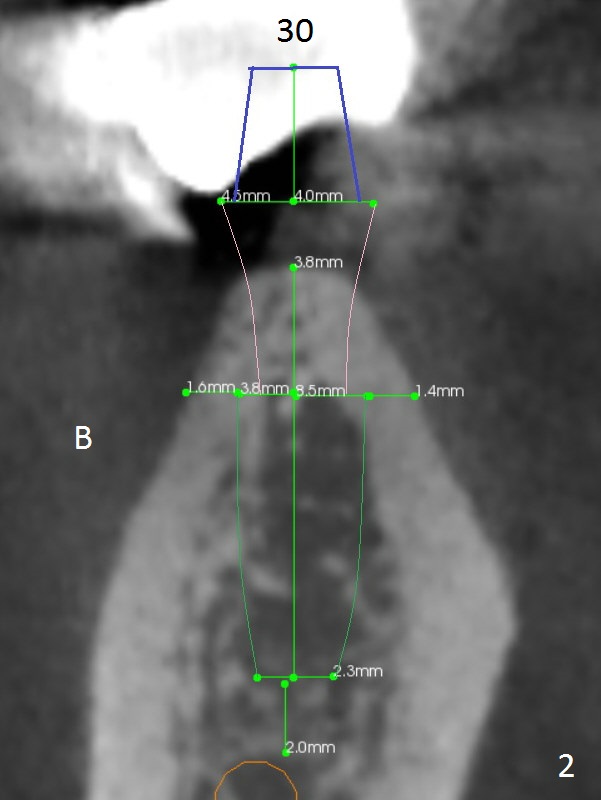

The ridge at #30 is pointed (Fig.2) and going to be resected (Fig.3 black area) to receive a narrow, short implant (3.8x8.5 mm). A splinted immediate provisional will be fabricated following placement of a 4.5x4(5) mm abutment at #30 (Fig.2,3). Take Alginate impression when the patient arrives in case the tooth #31 is also non-salvageable.